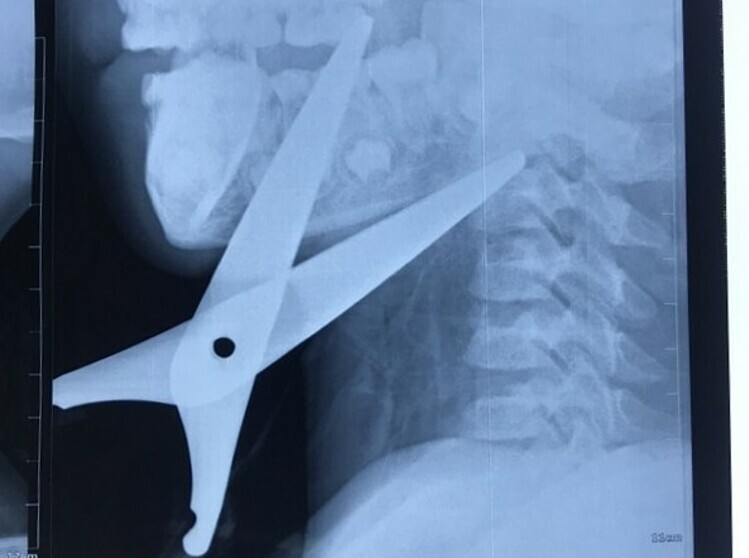

Cứu bé trai bị chiếc kéo đâm vào cổ

Hướng dẫn nuôi dạy con -  24/09/2020

Bé được đưa vào Bệnh viện Sản Nhi Ninh Bình cấp cứu hôm 20/9, chuyển tiếp đến Bệnh viện Nhi Trung ương trong tình trạng sốc, mất máu. Các bác sĩ chẩn...